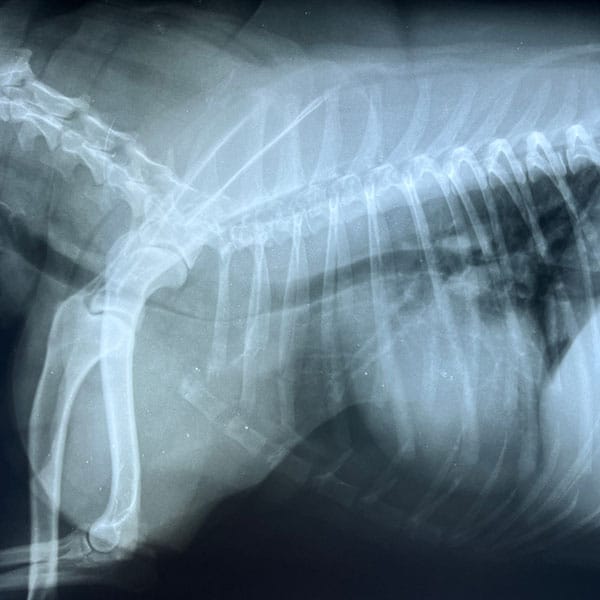

X-Ray & Diagnostic Imaging in Dacula

HPAH offers a state of the art digital X-ray machine which allows virtually no room for error and beautiful pictures that can be saved on a disc or emailed to a specialist if the need arises.